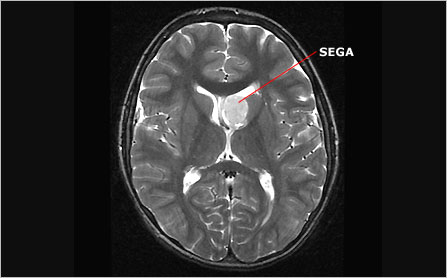

"There are three main anatomical features associated with TSC that alter the structure of the brain: cortical tubers, subependymal nodules (SENs), and subependymal giant cell astrocytomas (SEGAs). Cortical tubers form in and around the cerebral cortex, the brain's outermost layer. SENs and SEGAs form deeper within the brain, typically along the ependymal lining (walls) of the ventricles, the cavities containing cerebrospinal fluid.

SENs also differ from the relatively static tubers in that their growth can outpace that of the surrounding tissue, causing them to protrude into the cavities of the ventricles. While only 15 percent of SENs grow larger than 1 cm in diameter, those that do become classified as SEGAs and are cause for concern."

See pictures below. This ISN’T Oliver’s brain but, I will try to see if I can figure out how to upload his MRI and/or CT scan.